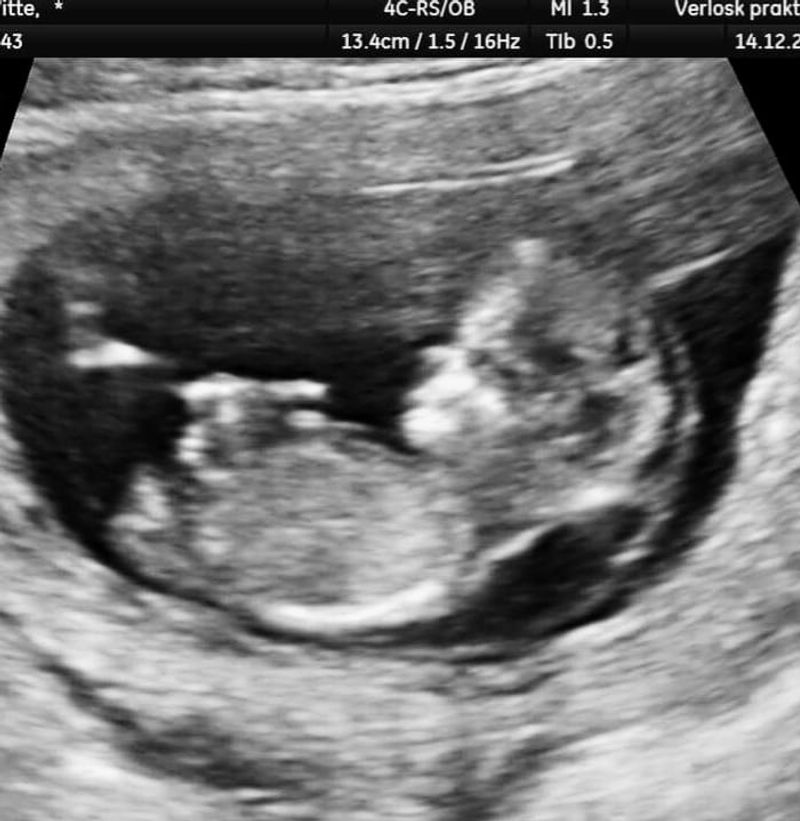

Met 12 weken zwangerschap had ik mijn tweede echo. Deze keer was ik erg zenuwachtig, maar ik kon niet plaatsen waarom. Met zweethanden ging ik op het bed liggen. Ik kreeg de steenkoude gel op mijn buik en kon mijn minime weer even bewonderen.

De verloskundige werd stil en meette alles goed op. Het bleef stil. Het leek wel een eeuwigheid te duren. Stotterend vertelde ze me dat ze iets bij het kindje zag, wat er eigenlijk niet hoorde. Zachtjes gaf ze aan dat mijn kindje erg veel vocht om zich heen had, wat ook wel een verdikte nekplooi wordt genoemd. Ze ging haar vocht meten en kwam uit op 12,5 mm bij haar nekje en rug. De verloskundige vertelde me dat een nekplooi maximaal 3,5 mm hoorde te zijn en mijn kindje had bijna 4 keer het dubbele. Ik werd doorgestuurd naar het MST Enschede voor een uitgebreide echo.